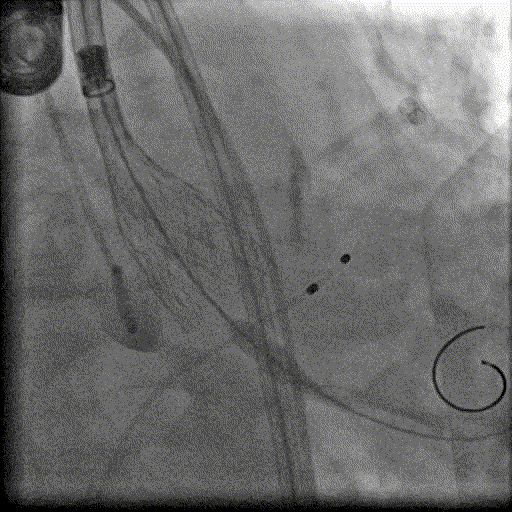

置入左室加硬导丝

23mm球囊预扩,无明显腰征及反流

输送系统过弓及跨瓣